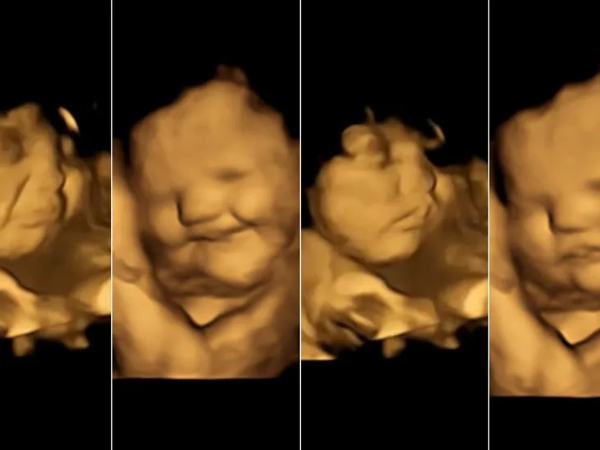

Bebês reagem a sabores de alimentos com expressões faciais ainda dentro da barriga, mostra estudo inédito com ultrassom 4D. Divulgação / Estudo Fetal Taste Preferences (FETAP), Universidade de Durham

As imagens obtidas durante o estudo permitiram que os pesquisadores observassem como os bebês reagem quando as mães comem determinados alimentos. Diante da cenoura, por exemplo, a maioria dos fetos exibiu um rosto sorridente, enquanto aqueles cuja mãe havia comido couve apresentaram cara de choro, afirmam os cientistas.